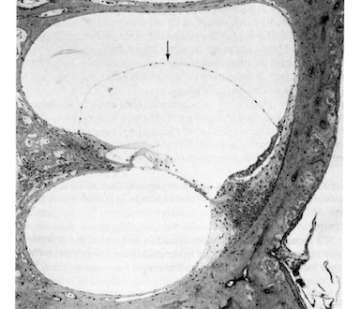

(B) Endolymphatic hydrops (arrow) are seen in middle turn of chinchilla cochlea four weeks following endotoxin instillation into the bulla. No cellular infiltration is seen in the perilymphatic space.